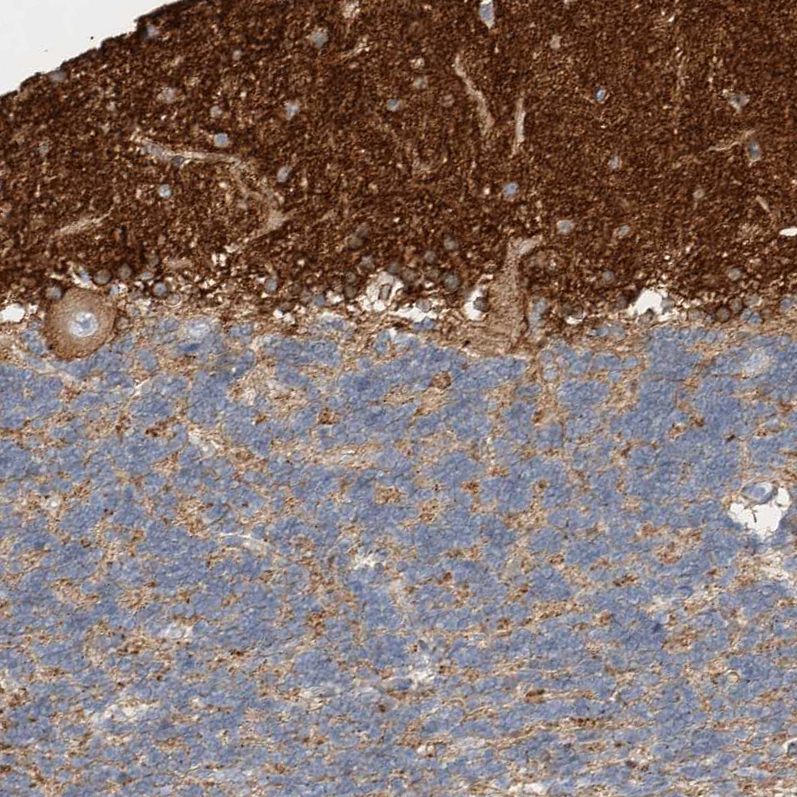

Immunohistochemistry analysis in human cerebral cortex and pancreas tissues using HPA022905 antibody. Corresponding SEPT4 RNA-seq data are presented for the same tissues.